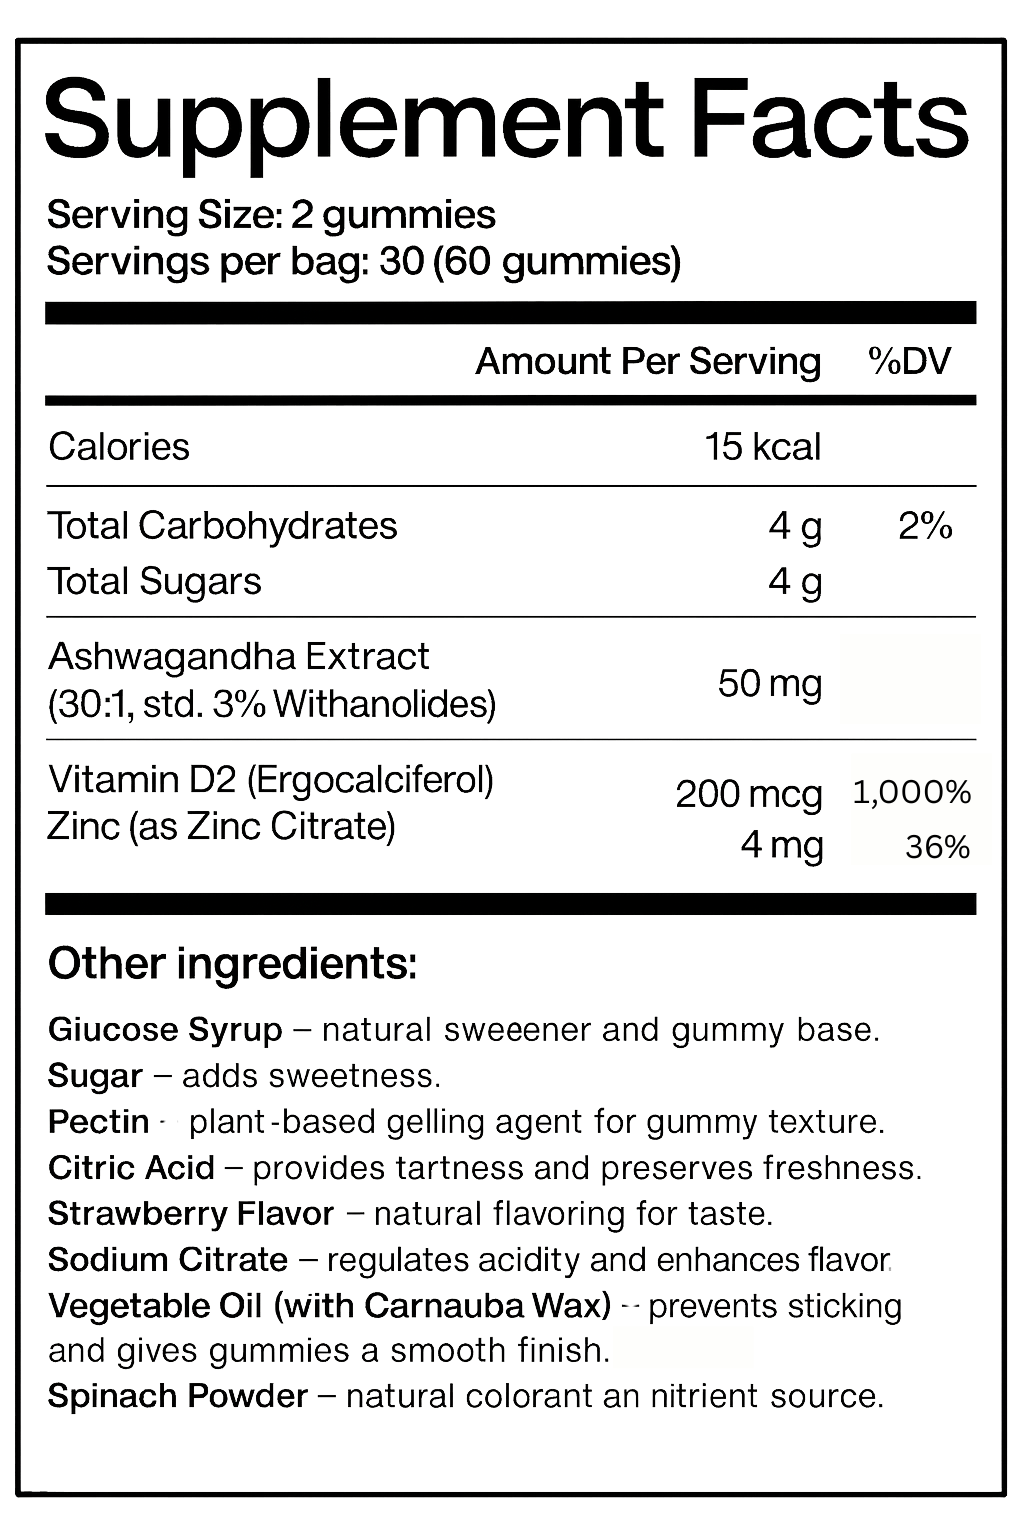

The clinically studied power of SmartCalm’s stress relief & balance system

The clinically studied power of SmartCalm’s stress relief & balance system